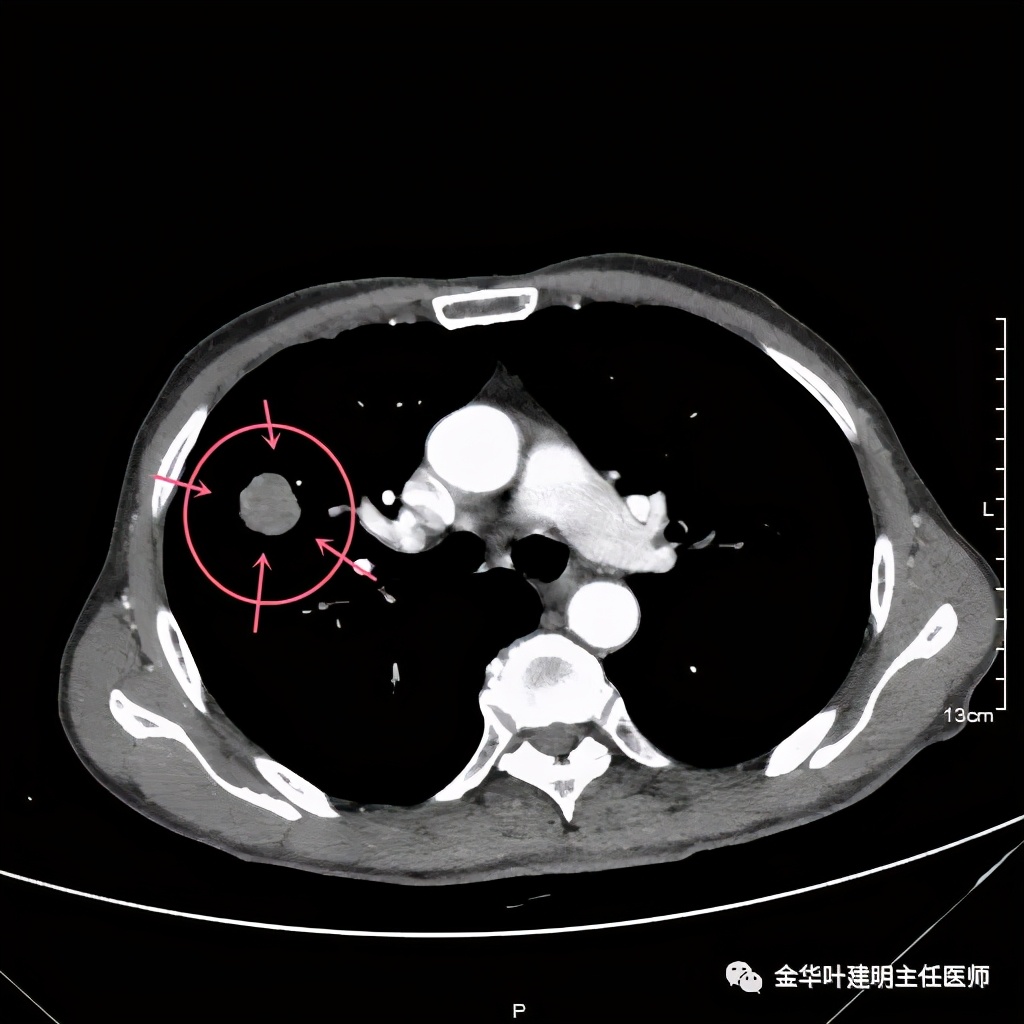

找到轻中度核异质细胞,要说确定肺癌还依据不够一点。因为病灶较大,若要手术,基本上应该肺叶切除的,所以当时他科主管医生与患方沟通后又进行了肺穿刺活检:

上图黄色箭头示穿刺针进入的地方,位置还是非常好的,应该容易穿到有价值的病变组织。但穿刺结果未见肿瘤:

病理不支持!怎么办?是抗炎治疗了先出院随访,还是仍手术?如果穿刺阴性仍予以手术,感觉穿刺失去了价值;如果不手术放回去,这样影像表现的病灶能放心认为是慢性炎吗?患者家属找到我,问我的意见,应该如何。我们先再来看看病灶的影像细节:

上图是穿刺时的某个层面,病灶的细毛刺征比较明显(蓝色箭头),病灶的边缘是不平的,而且有细短的毛刺样突向周围肺组织,这可是恶性的特征

桔色箭头示病灶周围血管征明显,有较粗的血管进入病灶,较细的也有